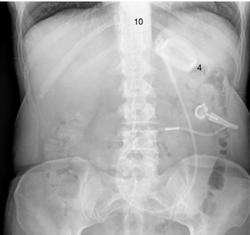

El síndrome del remanente gástrico es una secuela rara de obstrucción, pero el hecho de no reconocer su aparición puede provocar perforación, peritonitis y, posteriormente, la muerte. Las características incluyen dolor epigástrico, distensión, hipo, distensión y timpánica en la parte superior del abdomen, disnea o taquicardia. Una radiografía simple de abdomen puede mostrar una burbuja de aire gástrico y el diagnóstico se puede confirmar en la tomografía computarizada con contraste oral.